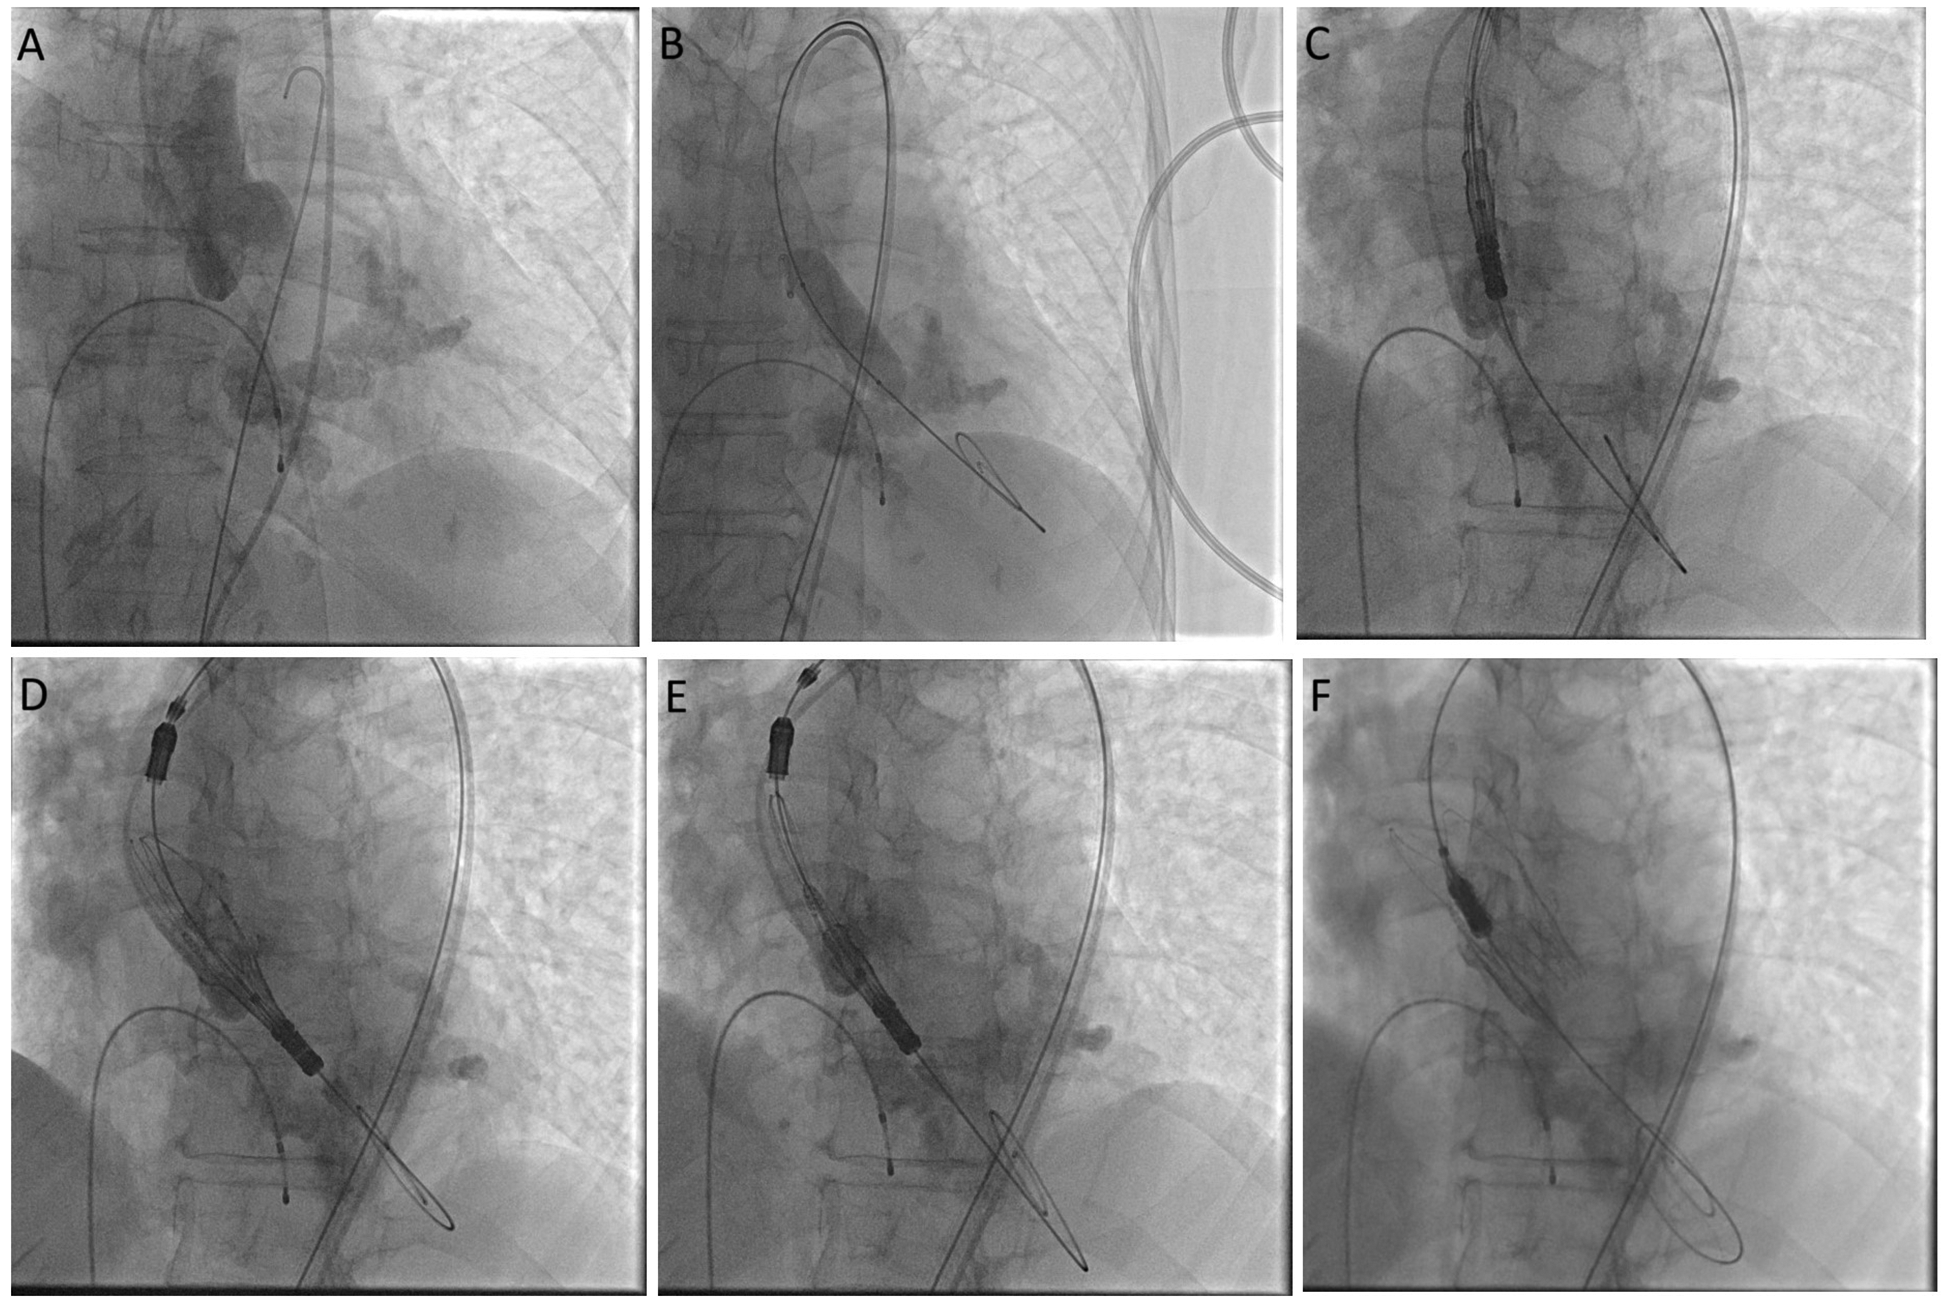

Figure 4

Cine images showing aortogram in cusp overlap view (A), steps of balloon valvuloplasty (B), and valve deployment (C–F).

After inducing general anesthesia, ultrasound-guided access to the left common femoral arterial (CFA) was obtained. Right CFA and femoral venous accesses were also obtained. Left CFA access was preclosed using two ProGlides. A 14 Fr sheath was inserted in the left CFA access. A 5 Fr pigtail catheter was inserted for hemodynamic monitoring. The valve was crossed with a JR4 Catheter and a straight tip 0.035 inch wire. The pre-procedure LV-Ao gradient was 40 mmHg. The JR catheter was exchanged to a pigtail 6 Fr catheter, and a Safari 0.038 inch guidewire was inserted over the pigtail catheter. Working projection was LAO 31° CRA 8°. Under rapid pacing, a balloon aortic valvuloplasty (BAV) was carried out using a VACS 16×40 mm balloon. A self-expanding THV (Acurate Neo2, 23 mm, Boston Scientific) was implanted in the supra-annular location of the leaflets. The valve was implanted using the commissural alignment technique (Figure 4). No immediate complications were seen. The LV-Ao gradient was 2 mmHg. No aortic insufficiency was noted. A lower aortogram was conducted, which showed a left iliac artery dissection and a contained perforation that was managed using local intermittent tamponade with balloon inflations.